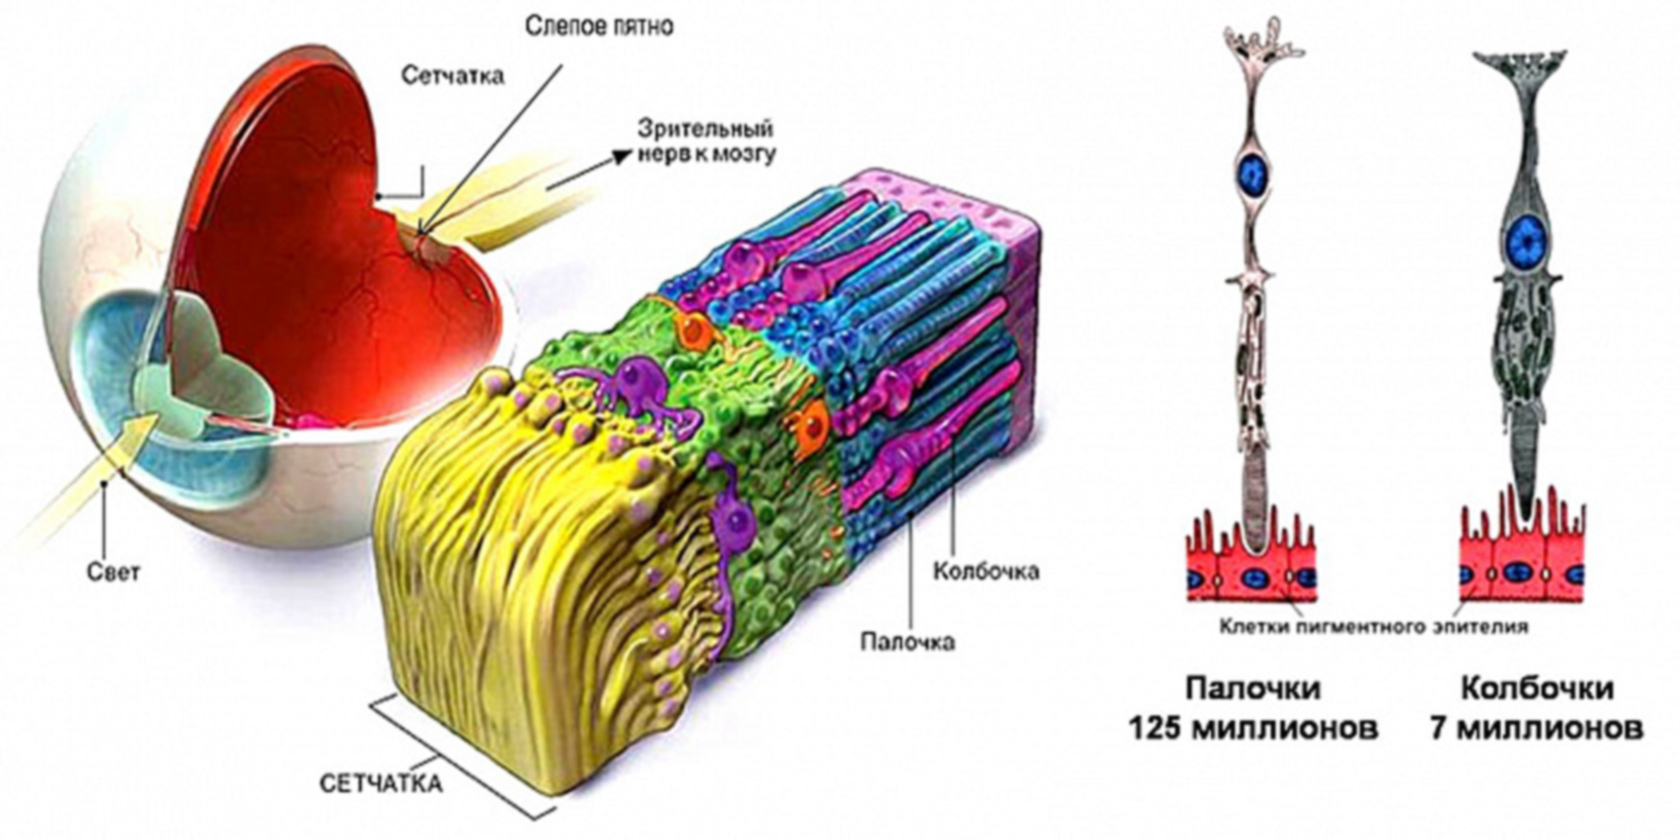

Изображения и анатомия сетчатки глаза